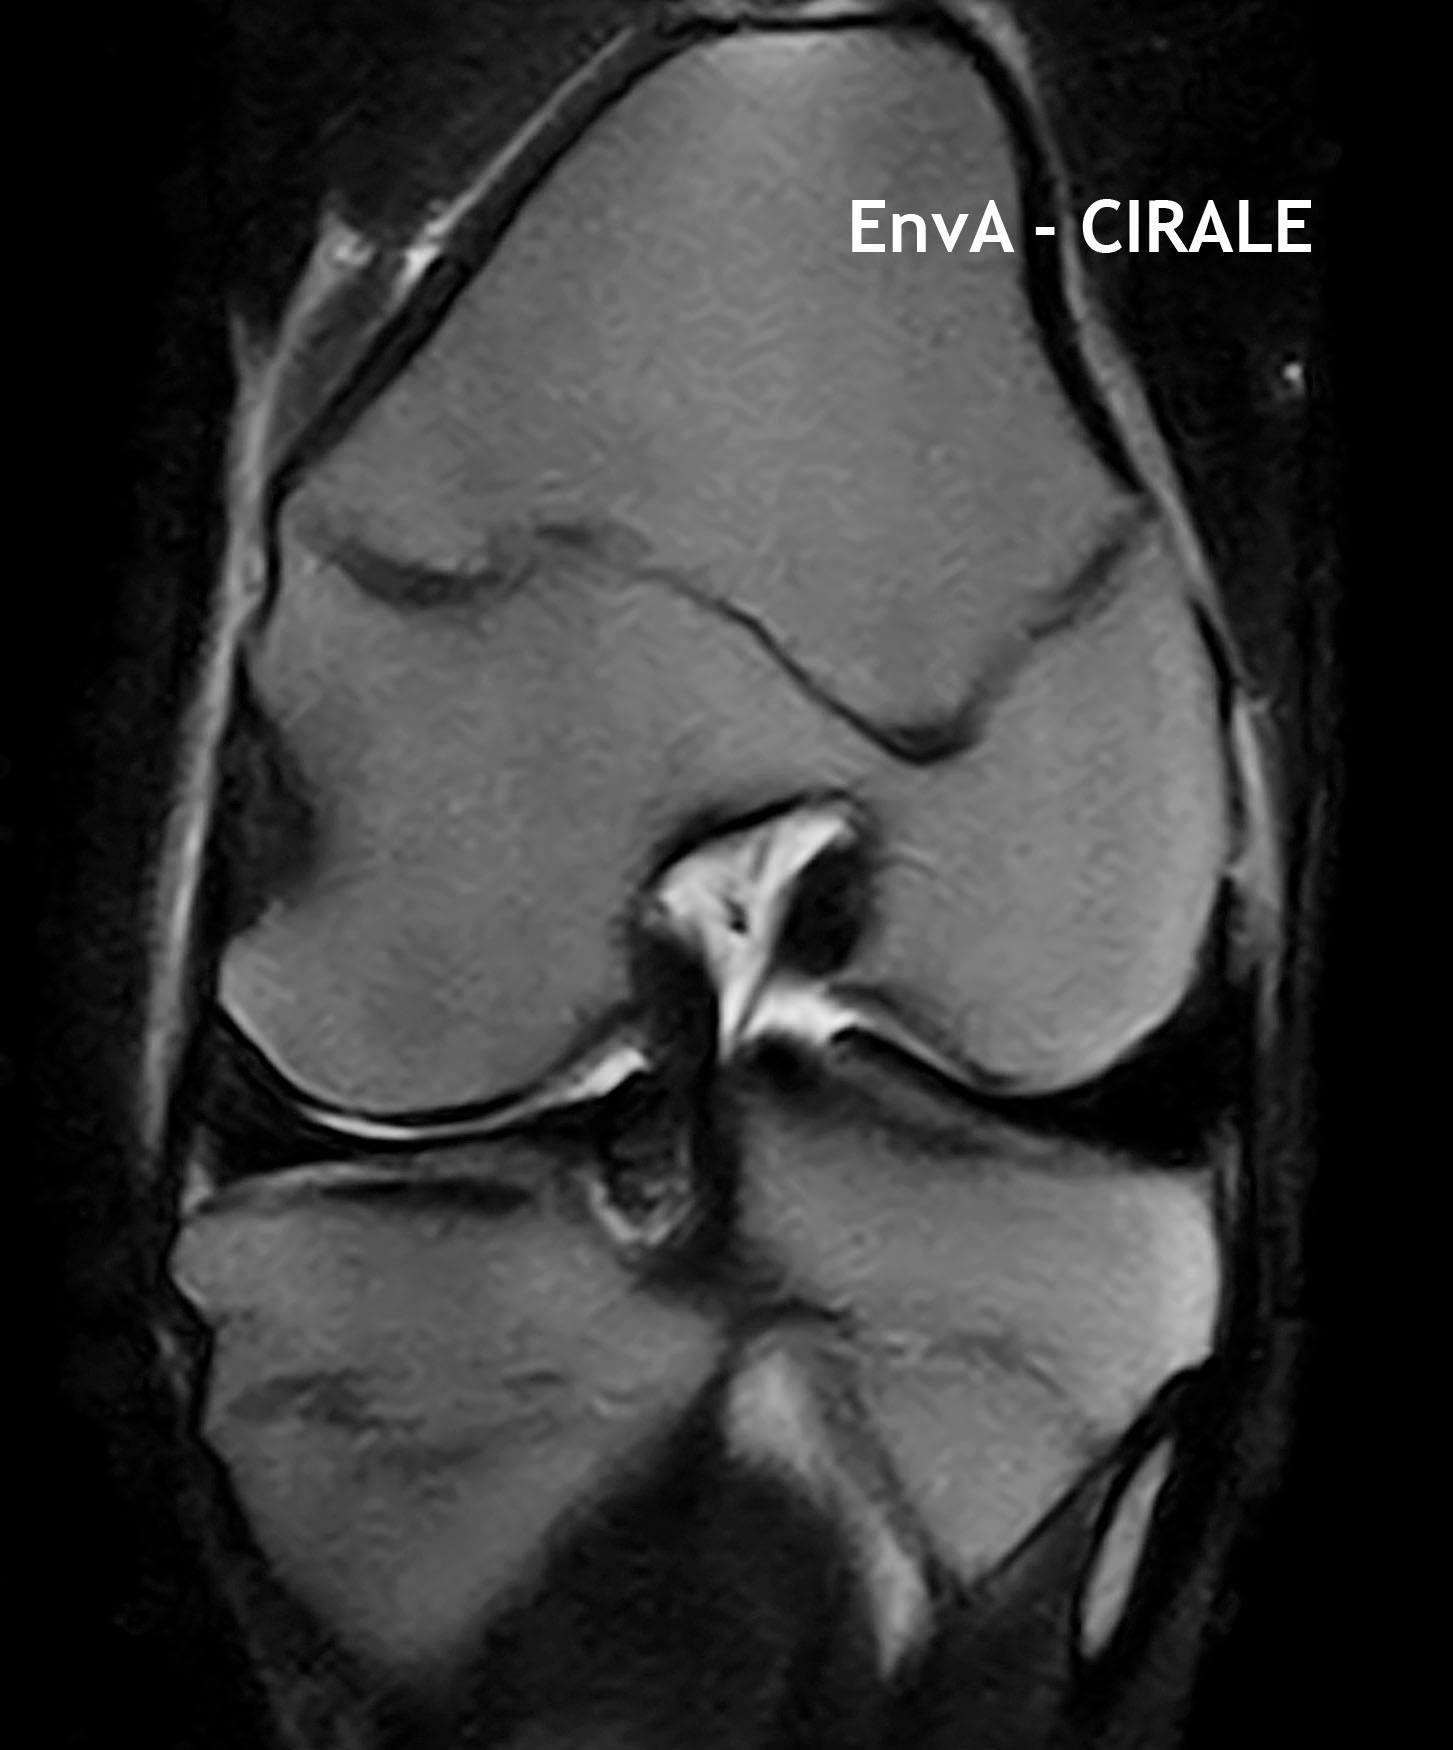

А помните, я упоминала про мою очередную поездку в ветшколу/клинику CIRALE ? Вот их новый ИРМ

Причем все не особо дорого, потому что работают студенты и ветеринары-стажеры по базовым манипуляциям, и часть расходов клиники покрывается программами Евросоюза и французским фондом EPERON (распределяющим в год 10 млн евро на инновации в конной отрасли, откуда деньги ? - с тотализатора). Лошадей туда везут со всей Европы, аж со Скандинавии. Особая слава у CIRALE - это диагностика проблем локомоторного аппарата, другими словами - проблемы всего, что влияет на движения (суставы, сухожильно-связочный, позвоночник, повреждения мягких тканей и тп).